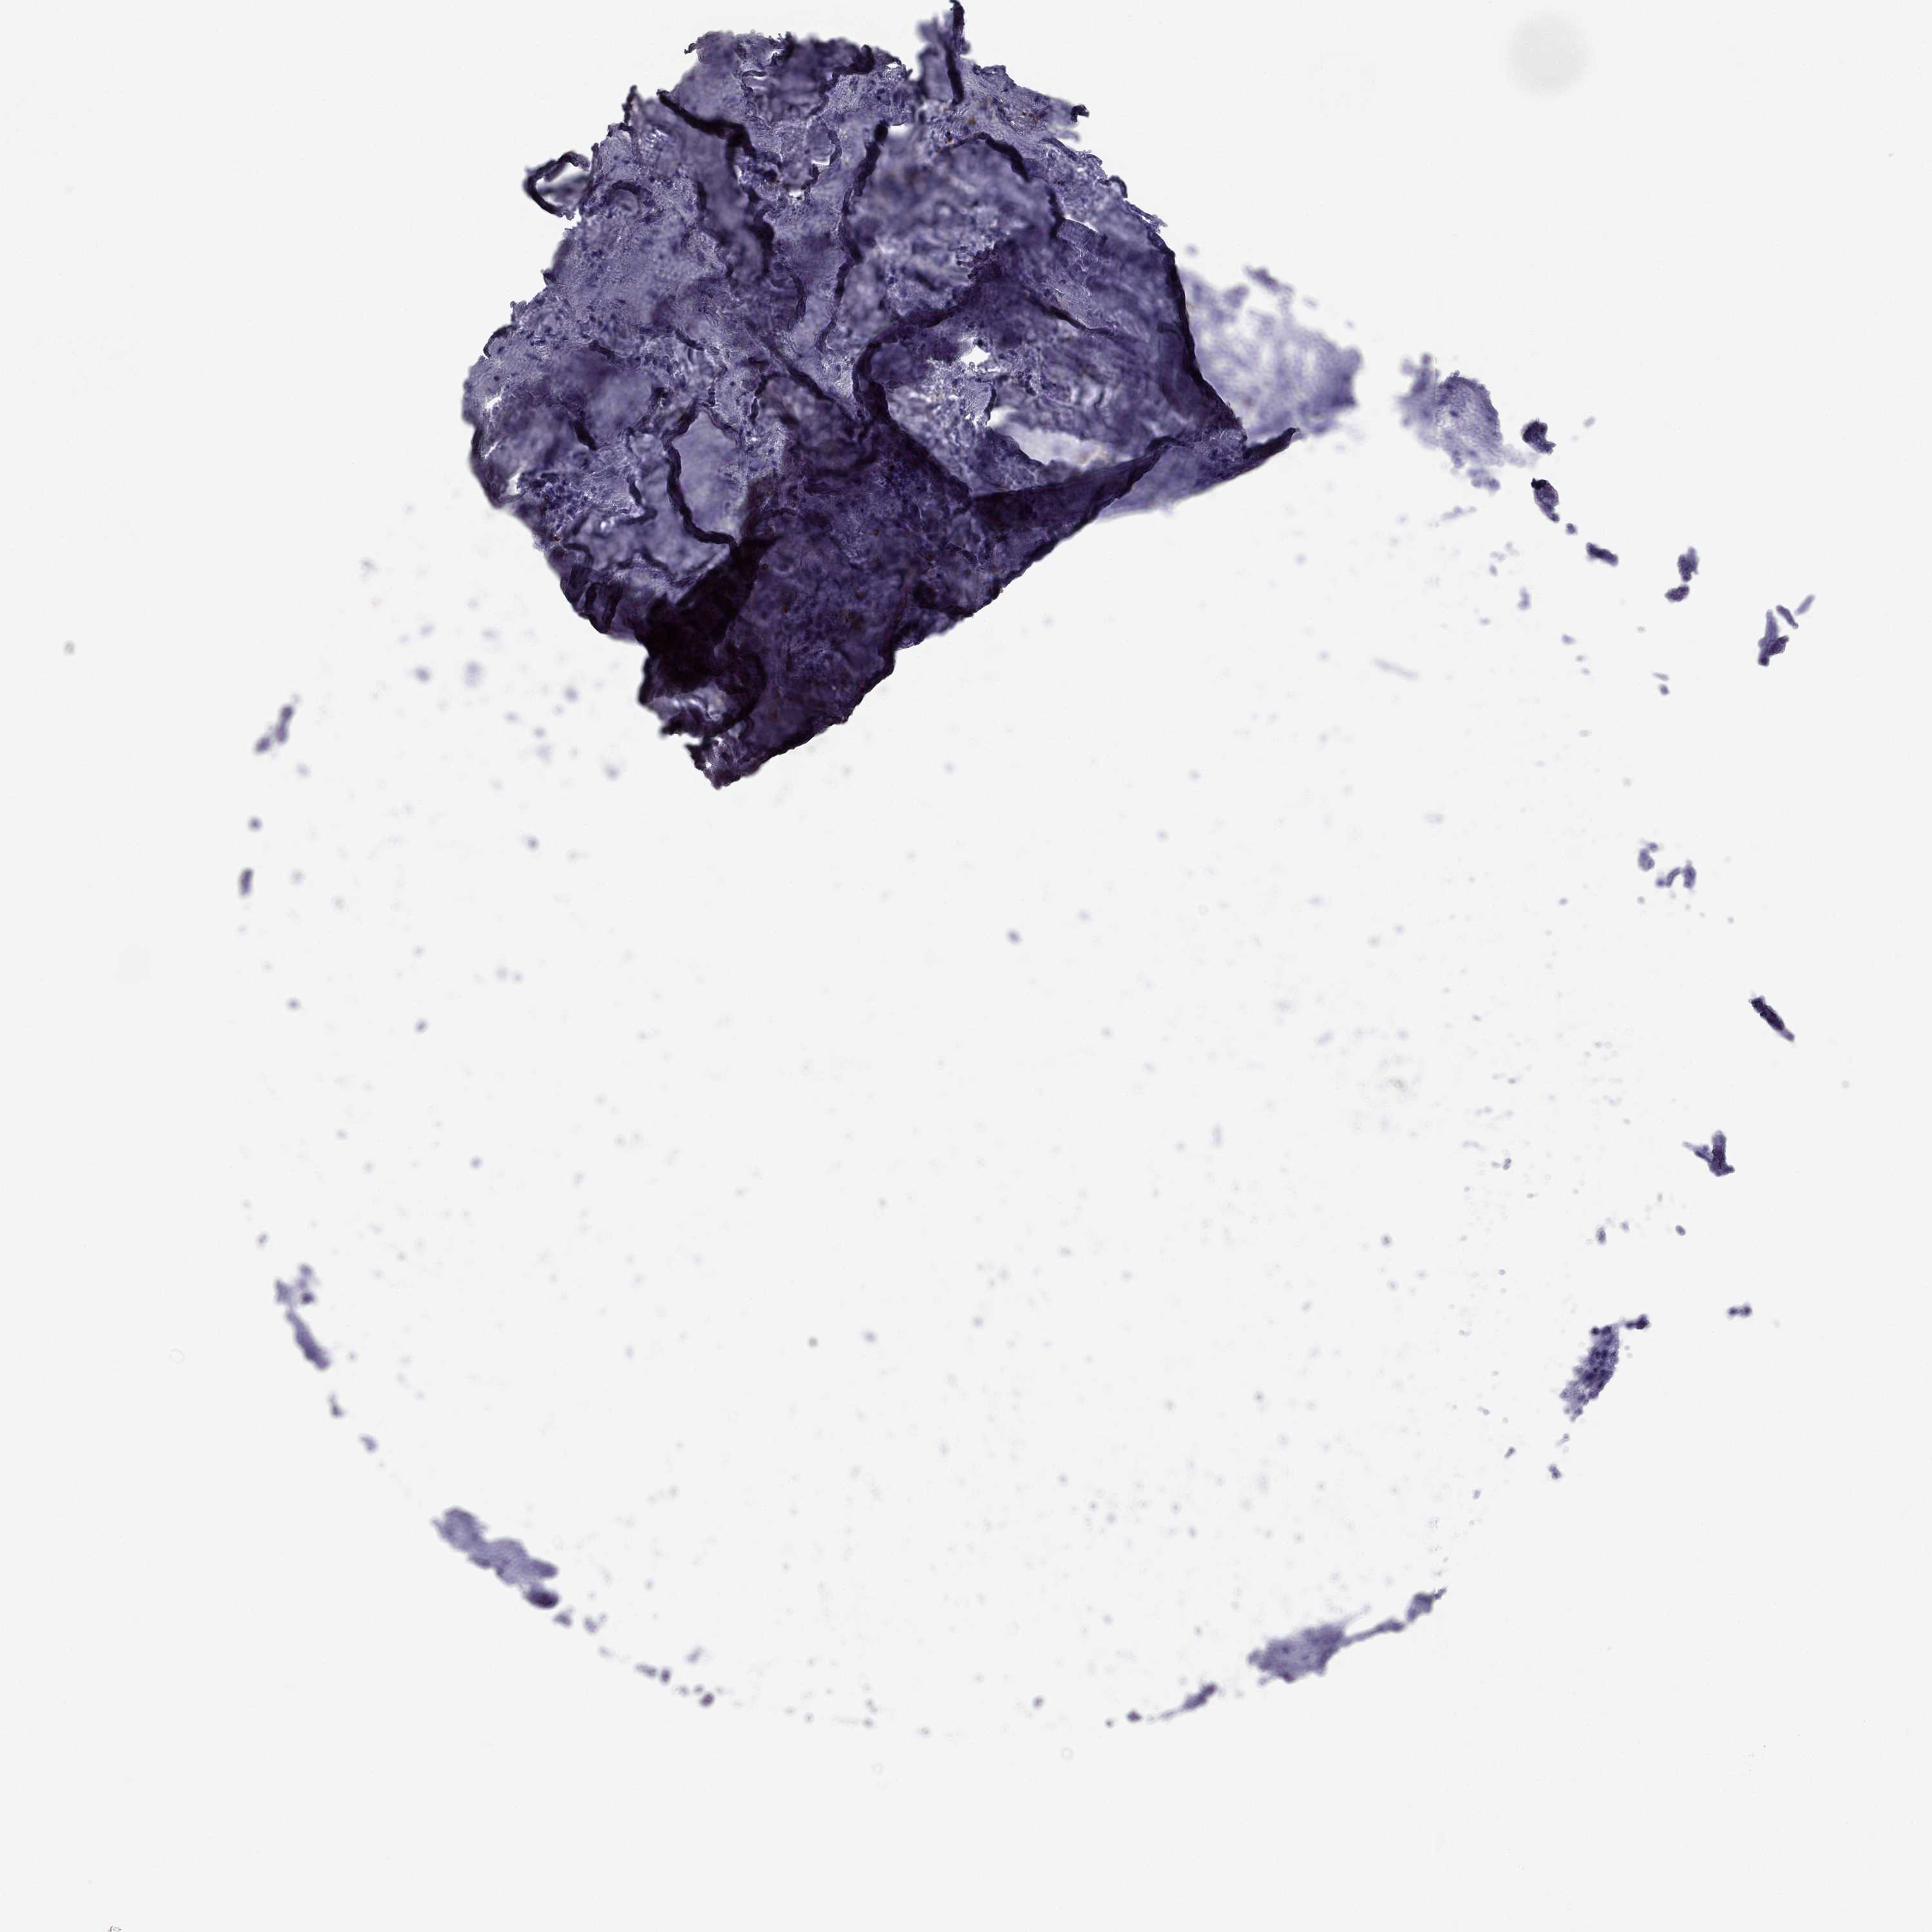

TCGA RNA samplesi

RNA-seq data is reported as average FPKM (number Fragments Per Kilobase of exon per Million reads), generated by the The Cancer Genome Atlas (TCGA) .

Normal distribution across the dataset is visualized with box plots, shown as median and 25th and 75th percentiles. Points are displayed as outliers if they are above or below 1.5 times the interquartile range. FPKM values of the individual samples are presented next to the box plot.

Average pTPM 1.3

Number of samples 521